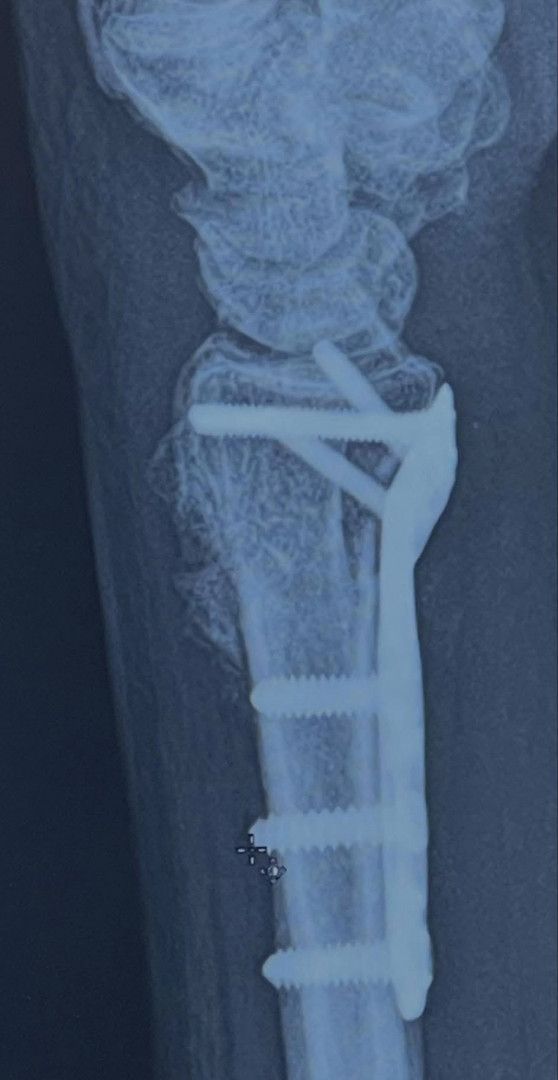

3/12/25 crash left me IMMOBILE with 107 FRACTURES I fought back. Now standing, fueled by nutrition, proof resilience is health

A passion for health and fitness was born in recovery. After a March 2025 car accident left me with 107 fractures and months in a wheelchair, I learned that movement, nutrition, and mindset are life-saving. Every workout and healthy choice is a gift. Fitness isn't about perfection, it's about honoring what my body has overcome. I want to live not just for myself but for my beautiful family, my friends and those who are in my circle cheering me on to get out of that wheelchair and live life.

After my March 12, 2025 accident, I was 53 and IMMOBILE for 3 1/2 months. Severe muscle atrophy, WEIGHT GAIN (25 lbs.), and the TOXIC effects of surgeries and pain meds pushed me to take control of my health. Through nutrition and intentional movement, PT, long walks with my husband or dog, Koko, I began healing my body from the inside out. I'm grateful for the inspiration, motivation, tips, love and support from my friends and coaches at the Looking Good - Feeling Good Facebook Community.